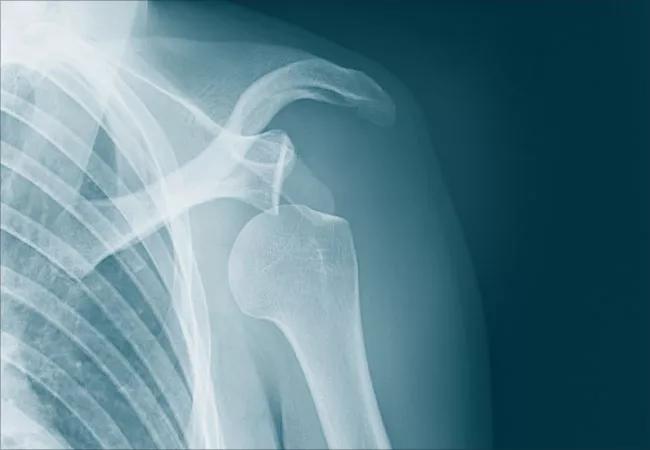

X-ray visual of a shoulder dislocation.

In some cases, the ball at the top of your upper arm bone (humerus) may come out of the socket only partially — called “subluxation.” This means that your shoulder moves past the normal location on the socket but is not completely out of place.

When it pops out completely, it’s known as dislocation. Both injuries can cause pain, arm weakness and swelling.